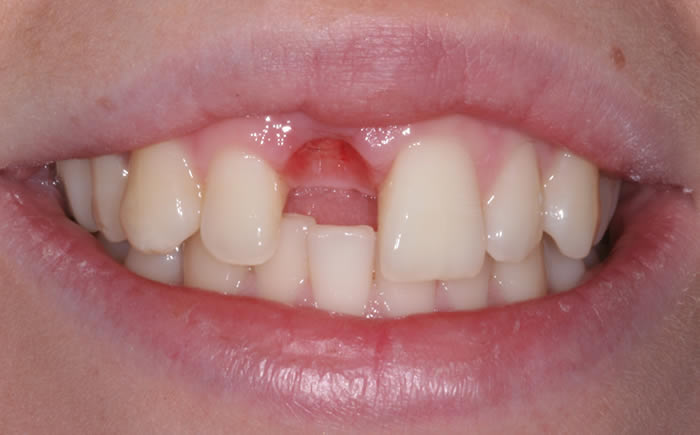

Before & After Gallery

More front teeth replaced by dental implants

Case Three (4 images)